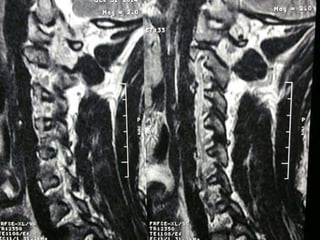

47 year old woman with 6 month h/o neck stiffness and pain with

left UE paresthesias into

The elbow forearm and hand especially IF/thumb

Note:the black line directly posterior to the vertebral bodies and relative

Thinning of spinal cord, note normal disc height